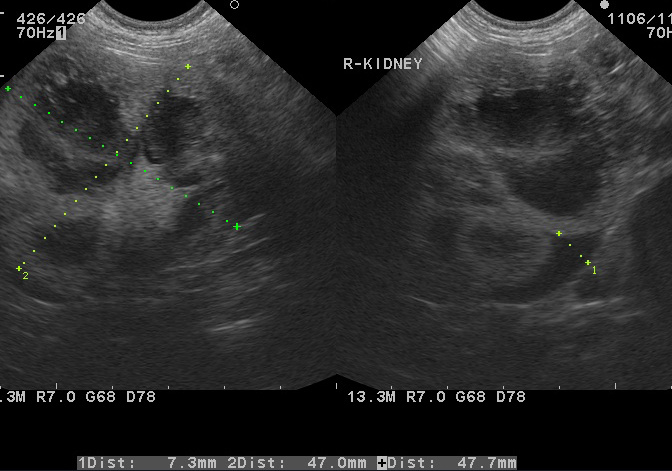

腹部エコー検査の読影について 京都市北区の動物病院 かもがわ動物クリニック